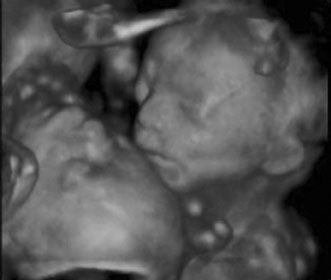

CHORIONIC VILLUS SAMPLING

The indications for CVS are similar for amniocentesis, except for a few rare genetic conditions that require chorionic villi for diagnosis.2 CVS is generally performed at 10 to 12 weeks' gestation. Similar to other first trimester methods, CVS allows for results earlier that can provide reassurance or allow for earlier and safer methods of pregnancy termination. Similar to amniocentesis, CVS is performed under ultrasound guidance. It can be performed either transabdominally or transcervically (Fig 4). Table 5 lists the contraindications and relative contraindications for CVS.

Fig. 4. Aspiration method of chorionic villi sampling. Ultrasound is used to localize the chorionic frondosum and guide the aspirating catheter into position. Syringe suction is used to trap and withdraw villi into the catheter.

Patients considering CVS should be counseled that there may be a slightly higher risk of pregnancy loss associated with CVS than with traditional amniocentesis. Pregnancy loss rates are reported to be 0.6% to 0.8% for CVS in excess of traditional amniocentesis. Loss may result from the procedure itself, but may incorporate the expected spontaneous loss rate between 9 and 16 weeks of gestation. According to the World Health Organization, the incidence of limb reduction defects are approximately 6 per 10,000, which is not significantly different from the incidence in the general population.2 Oromandibular-limb hypogenesis appeared to be more common with CVS, although highest when CVS is performed before 9 weeks' gestation.27–29 Similar to amniocentesis, cytogenetics can be available in 7 to 10 days (Fig. 5). FISH can also be used to provide a limited aneuploid screen in 24 hours.